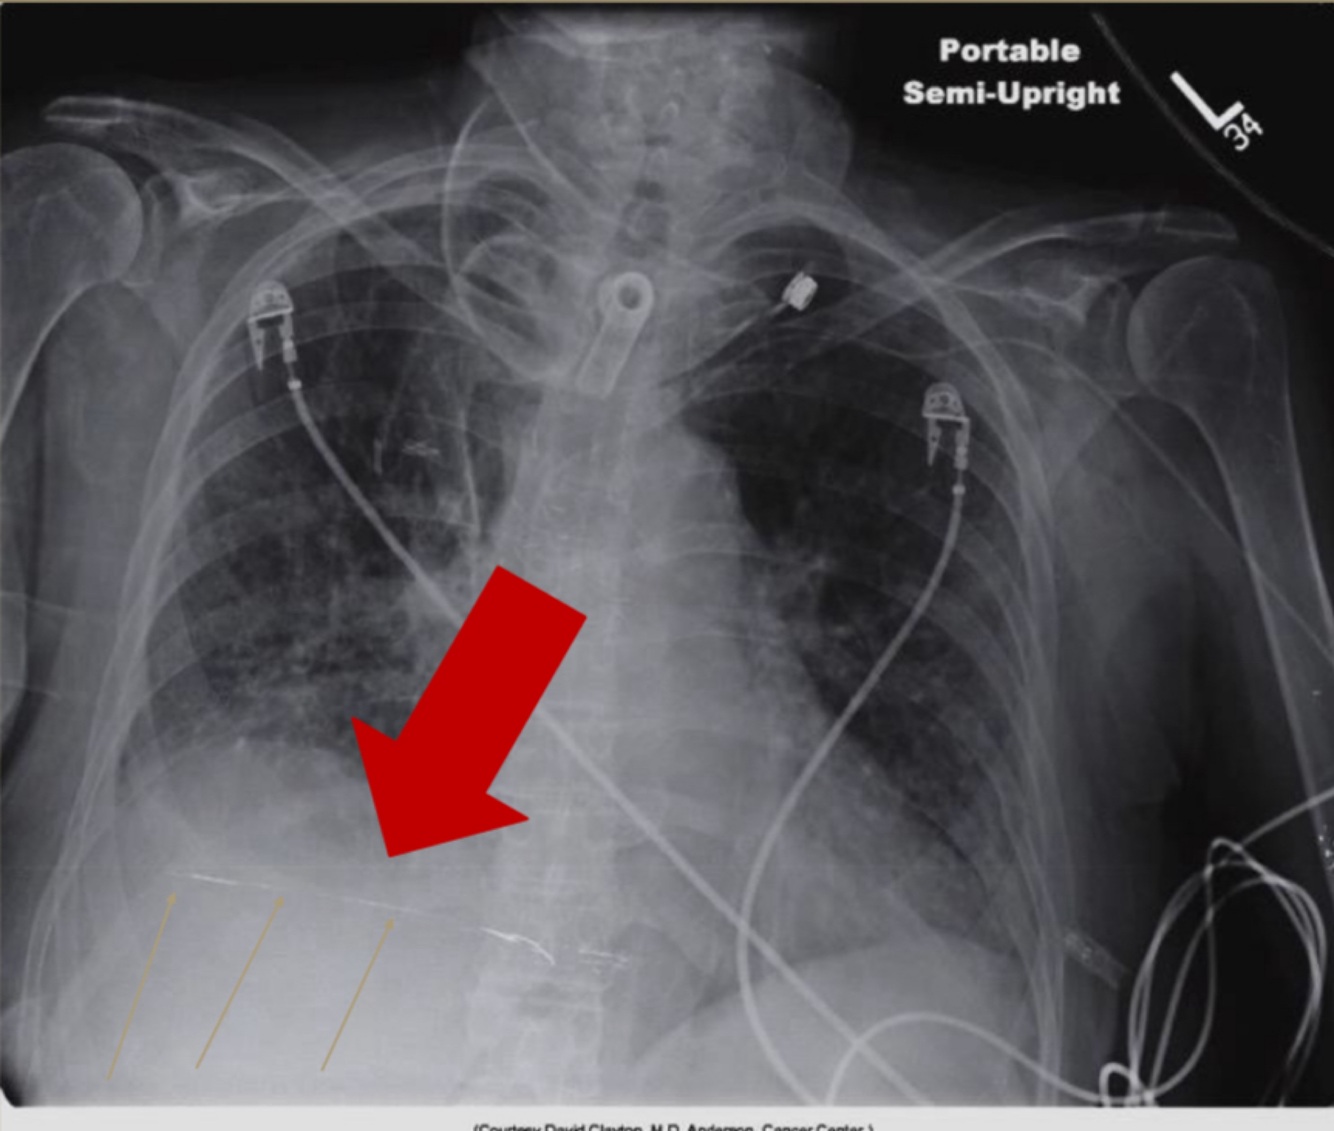

-The exposure field must be properly collimated, sized, and positioned. Exposure field recognition errors leads to histogram analysis errors because signal outside the exposure field is included in the histogram. The result is very dark or very light or very noisy images. -In DR, proper collimation has the added value of defining the image histogram. If improperly collimated, the histogram can be improperly analyzed, resulting in an artifact

34

-Normal chest x-ray of newborn • Proper cassette size and orientation • Center area of interest to IR • Collimate to area of interest

35